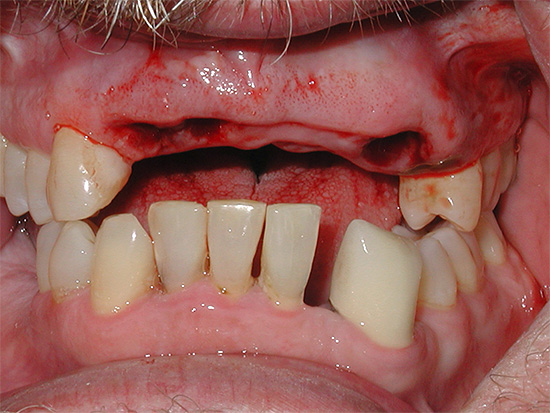

A foto a seguir mostra um exemplo de phlegmon odontogênico:

É por isso que é tão importante reconhecer o problema a tempo. Se, depois de arrancar um dente, o buraco estiver podre por algum motivo, não espere até que tudo resolva por si só - você precisará usar todos os meios possíveis para interromper essa complicação.